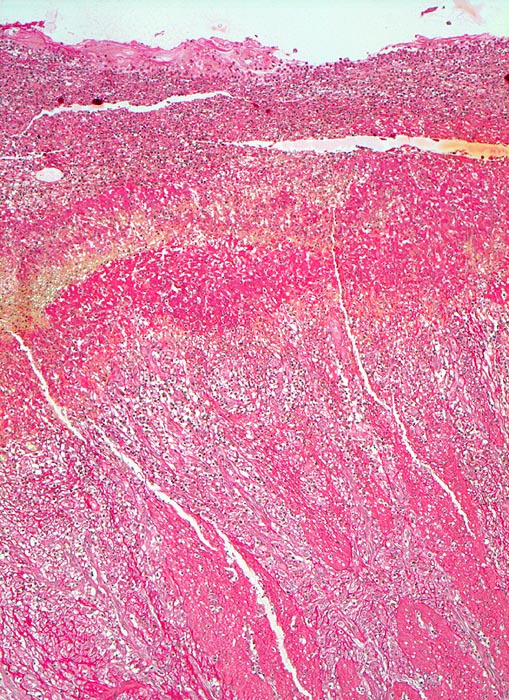

Das akute Ulkus ist rund, oval oder seltener polyzyklisch begrenzt und liegt meist im Schleimhautniveau. Das chronische Ulkus ist häufig kreisrund und im Längsschnitt trichter- oder treppenförmig. Die Schleimhautränder können lippenförmig über den Ulkusgrund hinausragen. Palpatorisch ist das chronische Ulkus aufgrund der narbigen Fibrose induriert. Die Schleimhautfalten laufen sternförmig auf das Ulkuszentrum zu. Das chronische Ulkus tritt zu 10%, das akute zu 25% multipel auf. Mikroskopisch zeigt das chronische Ulkus eine typische Schichtung (s. Bilder). Die Gefässe im Ulkusgrund zeigen eine starke Intimaproliferation mit teilweiser oder vollständiger Obliteration der Gefässlichtung. Morphologische Veränderungen in der übrigen Magenschleimhaut geben einen Hinweis auf die Ätiologie des Ulkus (Typ B oder C Gastritis).

• Antrumschleimhaut mit chronischer Gastritis am oberen Rand des Ulkus.

• Schichtung: Detritus, oranges Quellungsfibrinoid, Granulationsgewebe, Narbe.